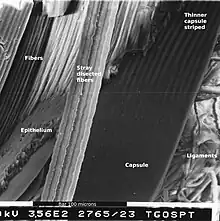

The lens capsule is a transparent membrane that surrounds the entire lens. The capsule is thinnest at the posterior pole with approximate thickness of 3.5μm. Average thickness at the equator is 7μm.[5][9] Anterior pole thickness increases with age from 11-15μm. The thickest portion is the annular region surrounding the anterior pole. This will also increases with age (from 13.5-16μm).[10] The ligaments suspending the lens form attachments in the equatorial area and more so just to the front and back of the equator.[11] There are tens of thousands of these ligaments in a mouse lens and for the most part they appear to connect directly to the lens capsule.[12]

As the lens grows throughout the life of most vertebrates the capsule is required to grow as well.[13] As shown in the accompanying micrographs and diagrams some ligament anchors have associated cells where they connect to the lens capsule. These cells have periodic cellular processes penetrating the capsule.

The structures in the images are consistent with the laying down of new capsular material required for growth. Even though the capsule is a highly elastic structure,[14] it contains no elastic fibers. Elasticity is because of the thick lamellar arrangement of the collagen fibers.[10]

During fetal development vascular lens capsule (tunica vasculosa lentis) develops from the mesenchyme that surrounds the lens.[16] It receives arterial blood supply from the hyaloid artery.[8] This blood supply slowly regress and vascular capsule disappear before birth. The disappearance of the anterior vascular capsule of the lens is useful in estimating the gestational age.[20] While the vascularization disappears during gestation the micrographs in this article show cells still active on the lens exterior after vascular regression. These cells may be the avascular portion of the original mesenchyme that surrounded the lens.